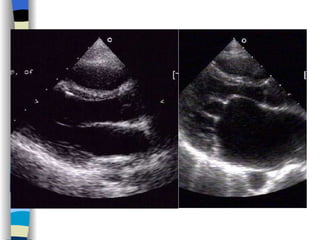

Echocardiography The most valuable technique for diagnosing MS, and determining its severity M-mode echo : Thickened, calcified leaflets open poorly, close slowly (EF slope ↓ ) The double peaks disappear Both leaflets move anteriorly during early diastole Two-dimensional echo: Fusion, thickening,  doming  of the valve leaflets, and poor leaflet separation in diastole;  mitral orifice area ↓

Doppler echo : Most accurate noninvasive technique for quantifying the severity of MS Spectrum Doppler: measure transvalvular gradient, MVA Color Doppler: display  high velocity color jet Provide other important information Cardiac chamber size (LA, RV) Left ventricular contractility Pulmonary arterial pressure Other coexisted valvular or congenital abnormalities  Mural thrombi

Echocardiography 1 、 Display anatomy of the mitral valve apparatus Useful in determining the etiology of MR ( 2D ) 2 、 Confirm the existence of MR Doppler   (color, spectrum): reveal high-velocity jet into LA during systole Sensitivity~100% Estimate the severity of MR < 4 cm2  Mild ( Color flow jet area )  4~8 cm2  Moderate  > 8 cm2  Severe 3 、 Measure cardiac chamber sizes, evaluate LV function, pulmonary artery pressure, provide data concerning other valvular lesions